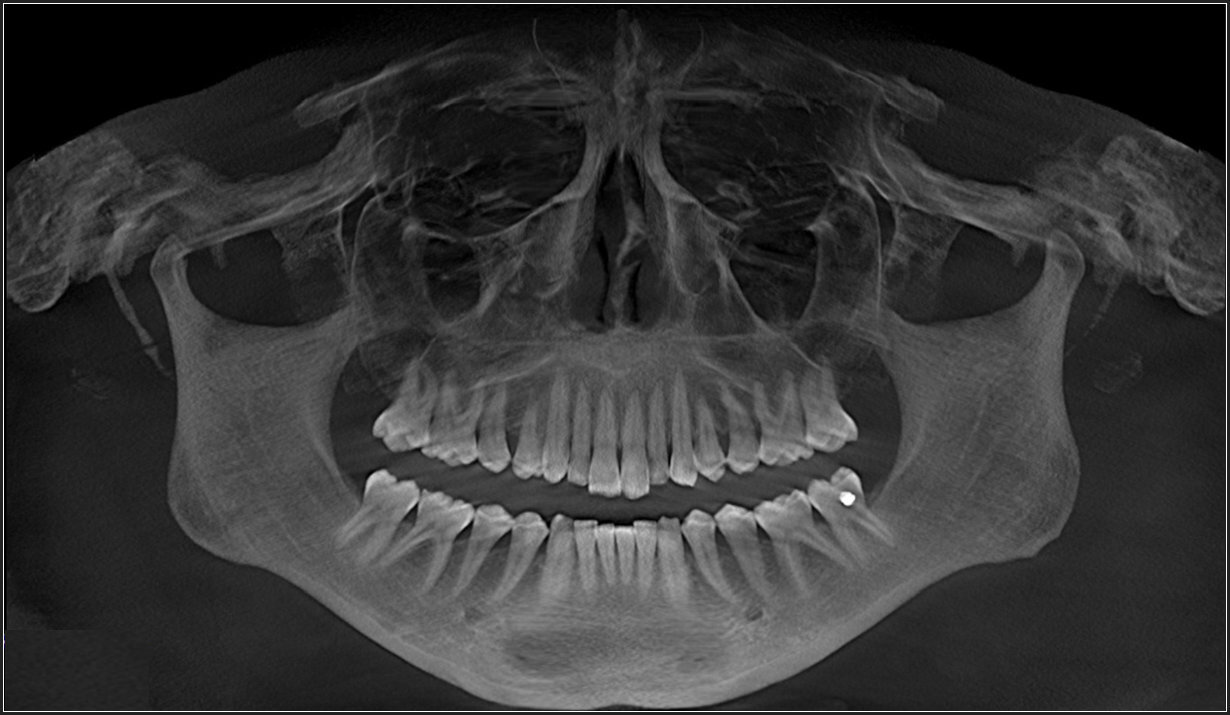

Each patient underwent a medical and dental history, a comprehensive clinical examination, standardized 3D-CBCT imaging, (Figure 1 & Figure 2) to confirm TMJs were stable and well adapted.